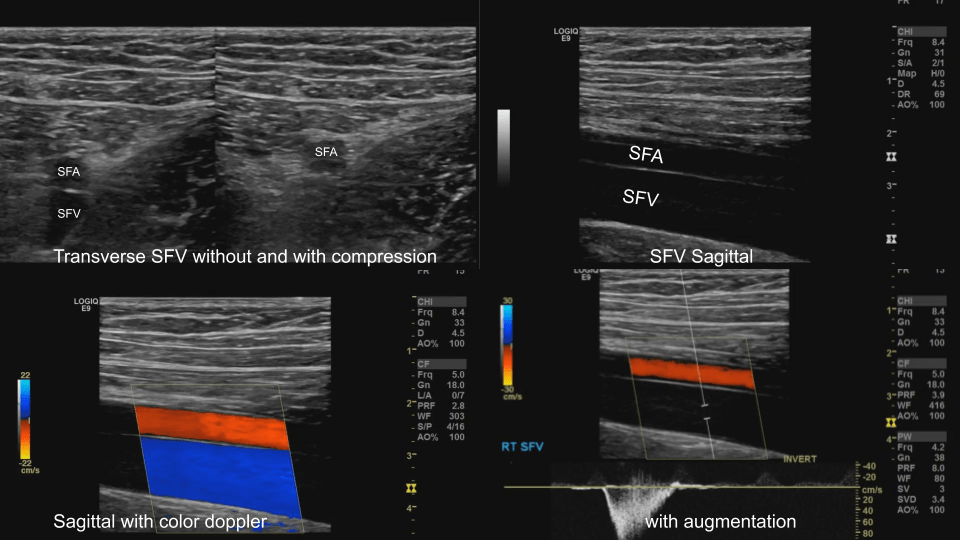

Femoral Vein: Dual image with compression, greyscale, color doppler, color doppler and pulsed wave doppler (scan proximal to distal)